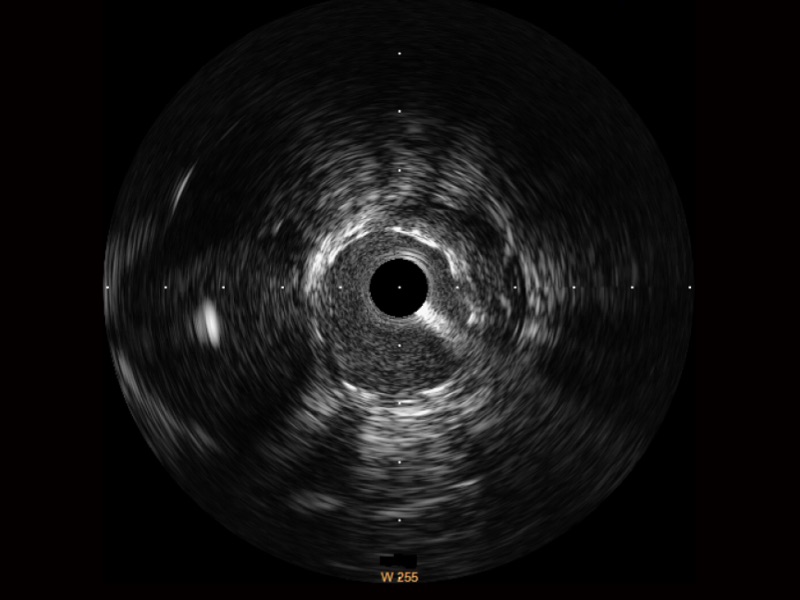

传统IVUS图像

对比传统IVUS导管成像,DB中国旗舰官方网站宽频IVUS图像的近场支架梁显影更细腻,远场中膜外血管仍清晰可辨,兼顾远中近,兼顾分辨力与穿透深度